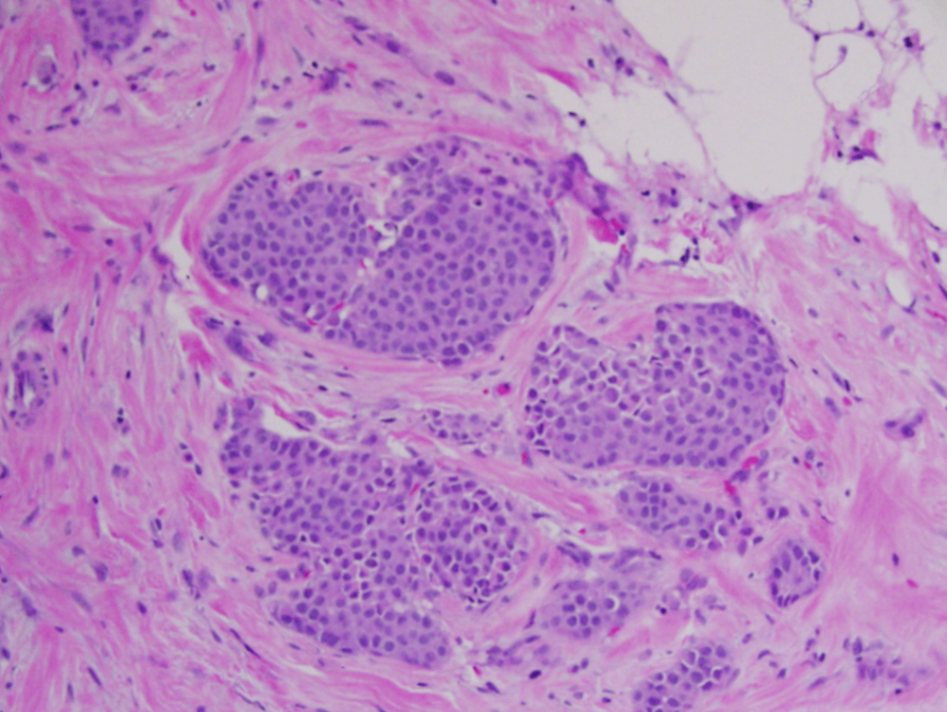

(2) 제자리소엽암종(lobular carcinoma in situ)

유관과 소엽 내에서 종양 세포들이 dyscohesive한 형태로 증식

- E-cadherin 결손: 세포 간 결합의 상실

• 석회화나 기질 반응과 같은 변화가 없어 일반적으로 유방 촬영에서 뚜렷한 병변이 관찰되지 않음 → 거의 대부분 조직검사에서 우연히 발견됨

• 조직학적 소견으로는 타원형 또는 원형의 핵과 작은 핵소체를 가진 균일한 세포군이 관찰됨. 이외로도 mucin-positive signet cell이 관찰됨

- 괴사 및 분비물, 그리고 석회화가 없음

Lobular carcinoma in situ, Wikipedia Commons